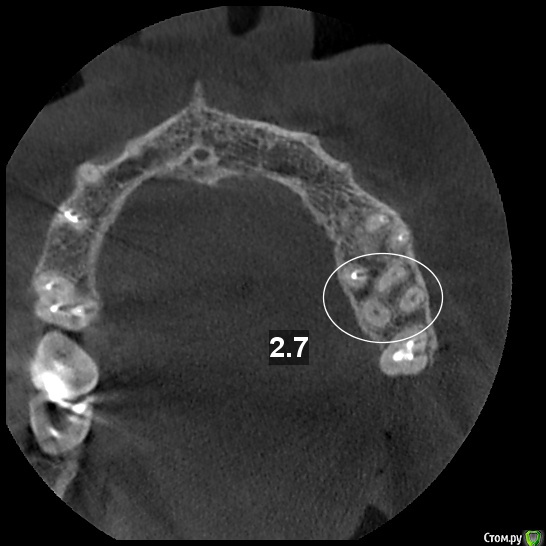

tatsiana.ma Опубликовано 29 ноября, 2016 Автор Поделиться Опубликовано 29 ноября, 2016 Плиииииииииииииз, очень нужна помощь знатоков.Сегодня опять была у стоматолога. Искали четвертый канал в зубе, в МЩК 2 канала.По данным КТ и скрину рентгенолога (см.рис1) в этом корне отдельные входы каналов с дальнейшим их слиянием в апикальной части.В итоге полость зуба раскрыта максимально, входа не видно и не чувствуется (см.рис 2). Затем расширено устье мщк, поиск шел внутри основного канала. На глубине ~5мм от входа найдена болезненная точка, файл за нее цепляется. Предположительно это вход в дополнительный канал, но пройти внутрь за эту точку дальше, чем на 2 мм не получается. Закрыли зуб лекарством, следующий прием через неделю.Может ли быть такая конфигурация, что в глубине основного канала открывается вход в канал дополнительный? или это вероятность что выходим не в канал, а на перфорацию? Ссылка на комментарий

DmitrySH Опубликовано 29 ноября, 2016 Поделиться Опубликовано 29 ноября, 2016 Извините, на КТ отмечены не каналы. Ссылка на комментарий

tatsiana.ma Опубликовано 29 ноября, 2016 Автор Поделиться Опубликовано 29 ноября, 2016 (изменено) Извините, на КТ отмечены не каналы. Вот этого я и боялась. Но этот срез сделан из КТ рентгенологом и она же ставила отметки на картинке и писала расшифровку. Что же она указала?.. Уже и зуб распахали весь, что дальше некуда((( Но боль при прохождении МЩК есть, вот сегодня эту точку боли нашли, но дальше чем 2 мм вглубь пройти пока не получается. То ли все-таки есть какой-то дополнительный канал (склерозирован?), то ли ковыряем неизвестно что. Я боюсь, чтобы не перфорировали стенку.На первоначальном снимке до депульпирования от середины корня к апексу вроде похоже на два канала в мщк. Да? Подскажите, пожалуйста. Изменено 29 ноября, 2016 пользователем tatsiana.ma Ссылка на комментарий

DmitrySH Опубликовано 29 ноября, 2016 Поделиться Опубликовано 29 ноября, 2016 На этом срезе кт четко видны только 3 канала. Что указано рентгенологом на прошлом срезе, затрудняюсь сказать. Выкладывайте весь диск с КТ Ссылка на комментарий